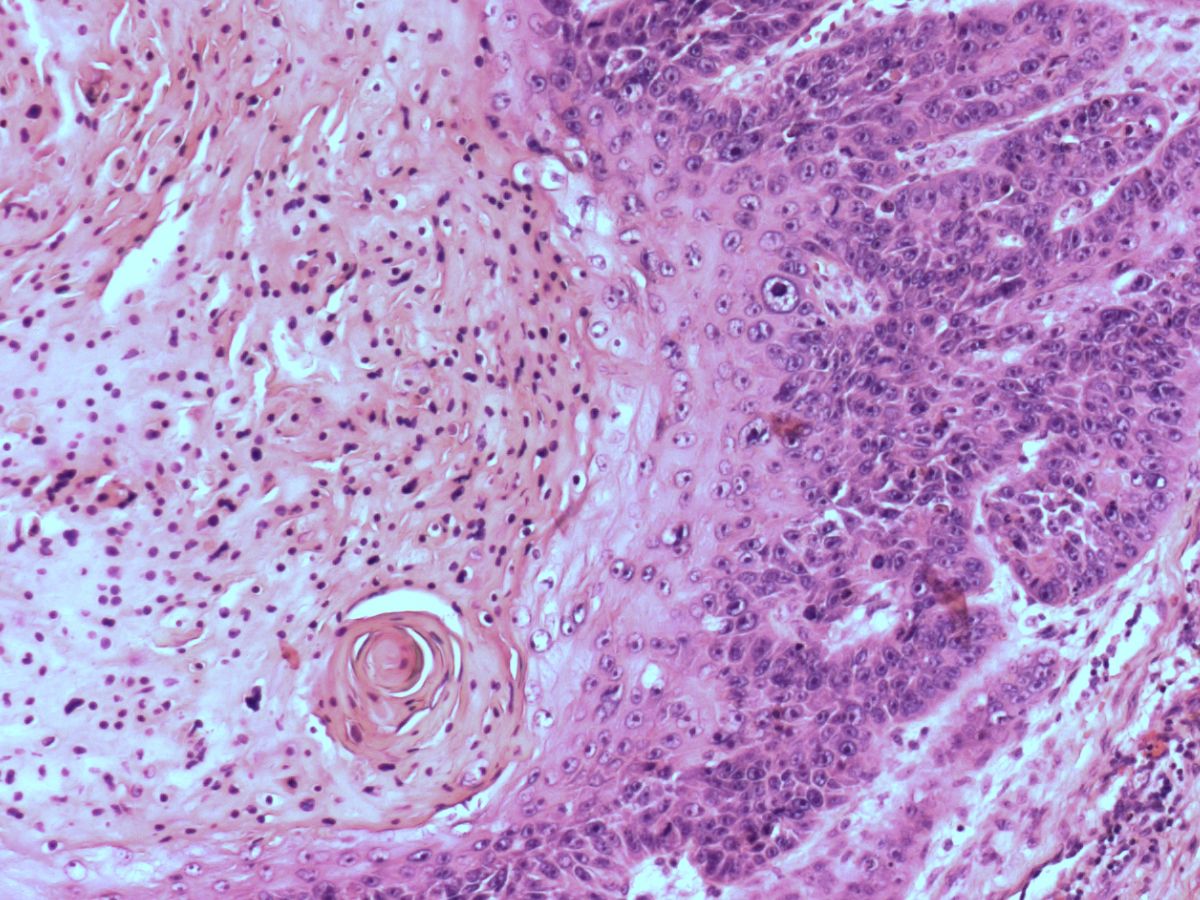

PA cutaneous

horn |

PA:Hyperkeratotische conus t.g.v.

langer bestaande hyperkeratose. Verder geen specifieke PA want een cutaneous

horn komt voor op basis van verschillende dermatosen zoals keratosis

actinica, verruca vulgaris, verruca filiformis, verruca seborroicum,

plaveiselcelcarcinoom, trichilemmoma, basaalcelcarcinoom.